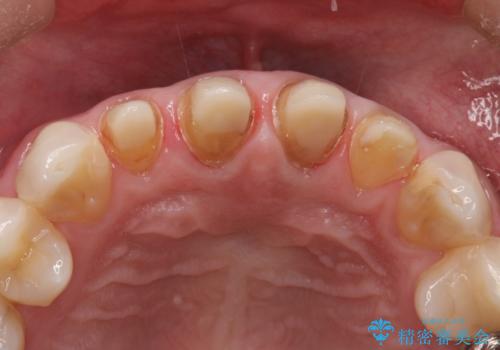

保険適用のかぶせ物が装着されており、適合も悪く、変色している状態でした。

土台からの、再治療を行い、オールセラミッククラウンの装着を行う計画としました。